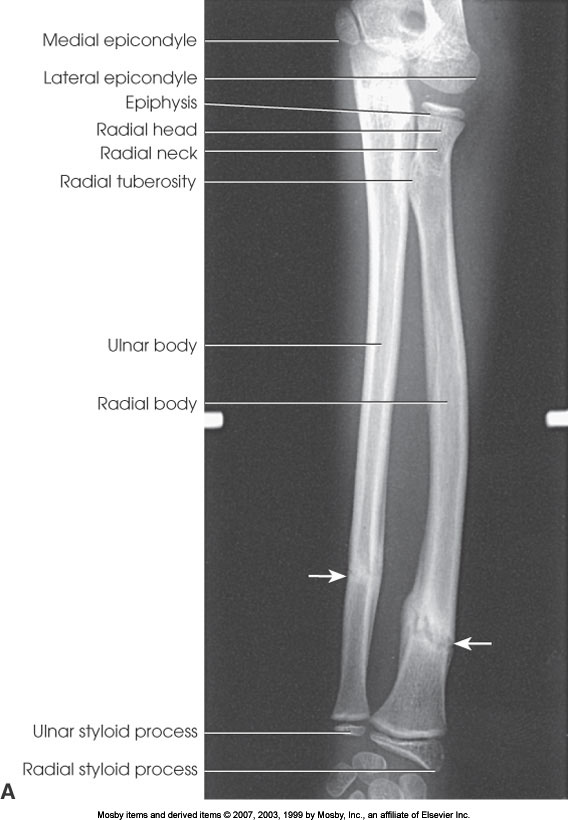

What position is demonstrated?

AP Forearm